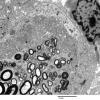

PERIPHERAL NEUROPATHY

4 AXONAL DEGENERATION

3 Electron Microscopy (3)